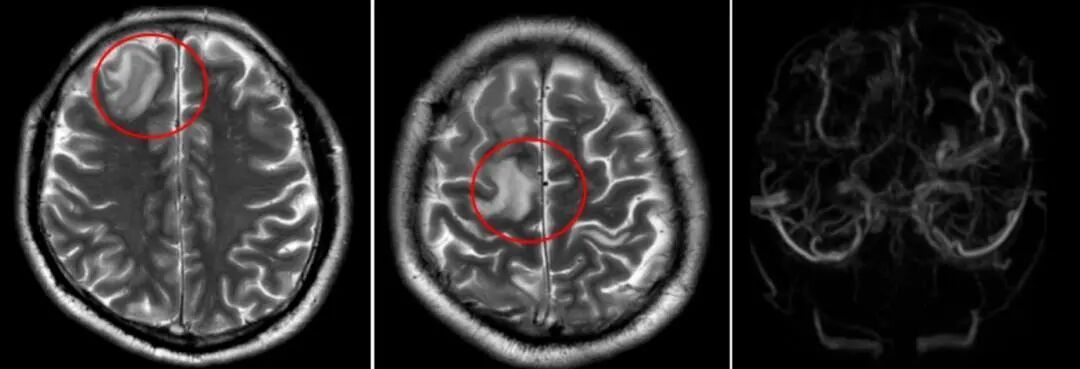

该院神经内二科医生陈婉洁接诊后,高度怀疑静脉窦血栓形成,紧急安排了相关检查。结果显示:右侧颈内静脉、双侧乙状窦、横窦、窦汇、上矢状窦多发血栓,伴静脉淤积性脑梗死。

患者头颅磁共振检查

“脑静脉窦血栓形成是一种相对罕见的中风类型,发病率虽不高,但后果严重。”医生用通俗的语言解释说,大脑里有一套“排水系统”——脑静脉和静脉窦,负责清除代谢废物、调节颅内压力等。正常情况下,血液流动顺畅,大脑“排水”正常。一旦形成血栓,静脉回流受阻,大脑“排水”异常,形成颅高压、静脉淤积性脑梗死或出血,引发头痛、呕吐、四肢抽搐、视物模糊、一侧肢体无力或麻木、意识模糊等症状,严重时甚至形成脑疝,危及生命。